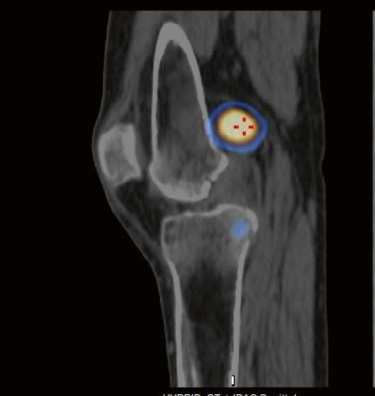

2. Fig. 2. Results of SPECT-CT of patient G. There is a focus of radiopharmaceutical accumulation in the region of the left knee joint | |